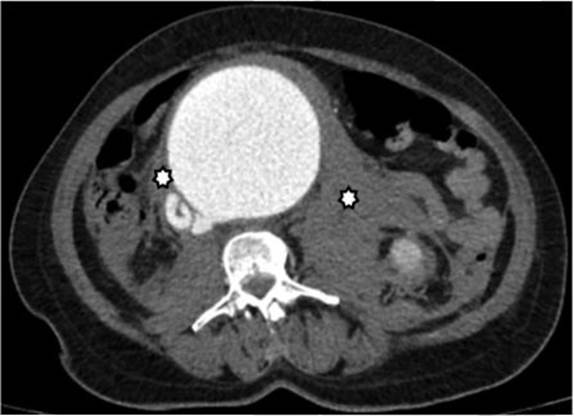

Fue posible identificar la extensión del aneurisma abdominal hasta la bifurcación de las arteria ilíacas adyacente a la VCI en todo su recorrido abdominal (Figura 2). Adicionalmente se observó ausencia de realce del parénquima renal derecho por hipoperfusión y cambios inflamatorios periaórticos con hematoma retroperitoneal asociado (Figuras 3 y 4).

Durante la evaluación de las imágenes, se documentó la presencia de úlceras arterioescleróticas penetrantes, así como la presencia de trombo mural en el recorrido de la aorta abdominal (Figuras 5 y 6).

Signos adicionales que soportan FAC son la hipoperfusión renal y la ruptura del aneurisma 5. El trabajo de Navdeep Singh y colaboradores concluyó que la presencia simultánea de contraste en la aorta y la VCI durante la fase arterial es el signo diagnóstico más importante; sin embargo, muy a menudo el aneurisma comprime la VCI, lo que dificulta la evaluación de este signo 5.